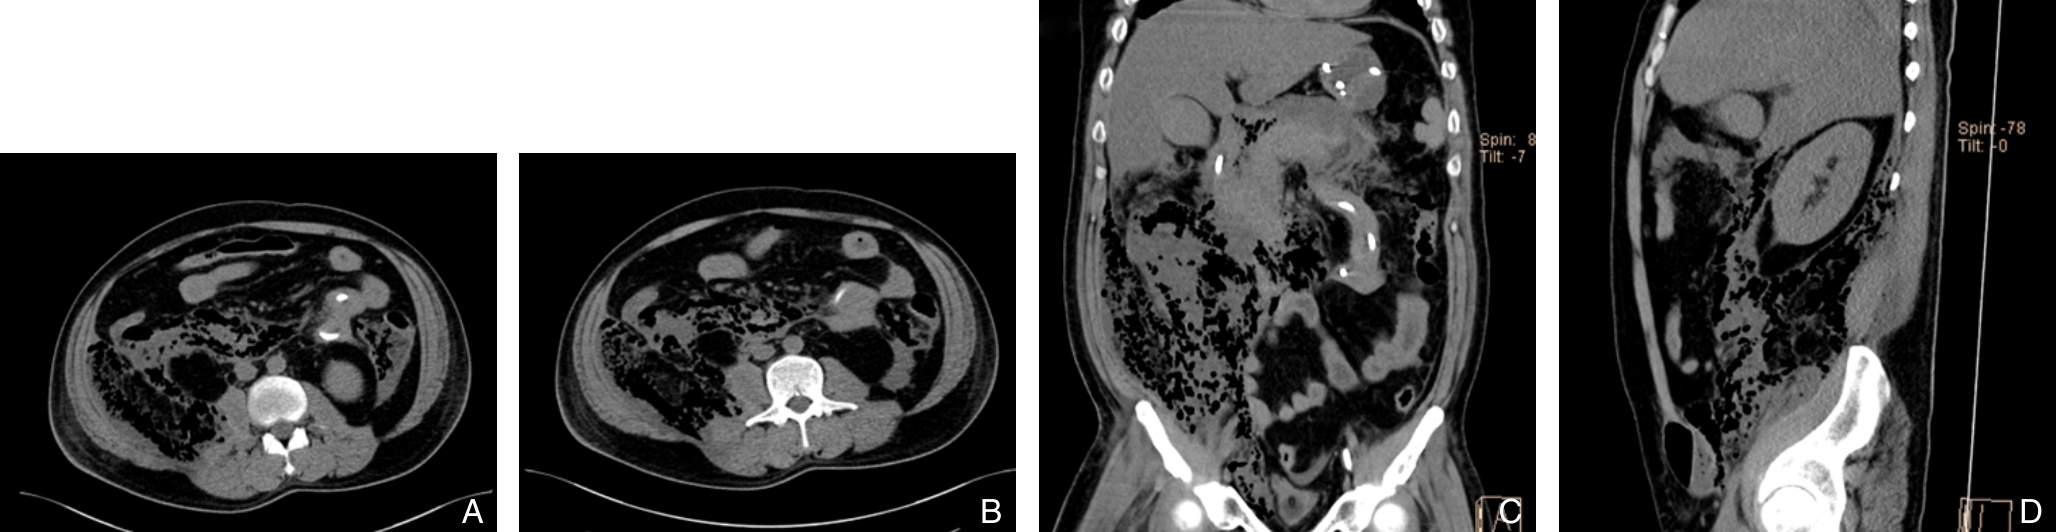

摘要:背景与目的 感染性坏死性胰腺炎(INP)尤其是弥漫性分布者病情凶险。对于首选干预策略(微创阶梯式vs.直接开腹坏死清除术)仍存在争议;此外“湿性”与“干性”坏死,以及是否合并重症急性胰腺炎(SAP)对策略选择的影响尚不明确。本研究旨在比较两种策略在弥漫性分布INP中的疗效与安全性,并评估基于CT影像的坏死类型与SAP状态在决策中的指导价值。方法 回顾性分析2012年1月—2023年3月中南大学湘雅三医院收治的458例弥漫分布INP患者,其中微创阶梯式组256例,直接开腹组202例。按基于决定因素的分类法定义SAP,依据CT特征将坏死分为“湿性”和“干性”。比较两组主要终点事件(死亡或严重并发症复合终点)及次要终点事件(死亡率、住院时间、切口并发症等),并进行亚组分析。结果 总体上,直接开腹组主要终点事件发生率(62.4% vs. 48.1%,P=0.003)及死亡率(27.2% vs. 16.8%,P=0.008)均高于微创阶梯式组。SAP亚组中,阶梯式治疗主要终点事件发生率更低(66.7% vs. 97.7%,P=0.003)。非SAP患者中,两组主要终点事件发生率相近,但直接开腹组住院时间更短[(36.5±10.4)d vs.(45.6±18.6)d,P<0.001],切口感染和切口疝更常见(均P<0.001)。多因素分析显示,感染出现时间、积液特征、气泡征及坏死部位为阶梯式治疗长期住院的独立预测因素(均P<0.05)。“湿性”坏死患者经微创阶梯式治疗获益更大,而“干性”坏死患者经直接开腹治疗住院时间更短。结论 对于弥漫性分布的INP,治疗策略应基于SAP状态与坏死液化/影像特征个体化选择:阶梯式微创优先适用于SAP患者及CT示“湿性”坏死者;对于“干性”坏死(尤其液化不充分者),直接开腹清创在缩短住院时间与降低某些主要终点事件方面更具优势,但需警惕切口感染与切口疝等并发症。CT影像学特征与SAP分类可作为风险分层工具,指导个体化干预时机与方式。

2025, 34(9):1923-1933. doi: 10.7659/j.issn.1005-6947.250306